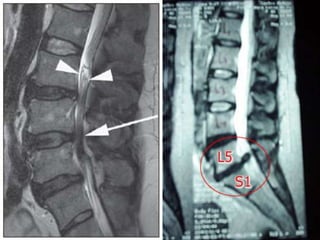

• A ressonânciamagnética (RM) é muitas vezes o primeiro exame de imagem feito para avaliar a medula espinhal e as raízes nervosas. No entanto, na ocasião, um paciente tem um dispositivo médico, como um marca-passo cardíaco, que podem impedi-lo de passar por ressonância magnética. • Entre as vantagens da RM temos uma melhor definição anatômica das estruturas cerebrais, a capacidade multiplanar, a RM pode demonstrar fluxo sanguíneo ou liquórico, tem uma melhor visualização da fossa posterior e do conteúdo intra-espinhal e ausência de radiação ionizante.

• 44.

RMN medula espinhal cervical –cortes sagitais, lesão medular